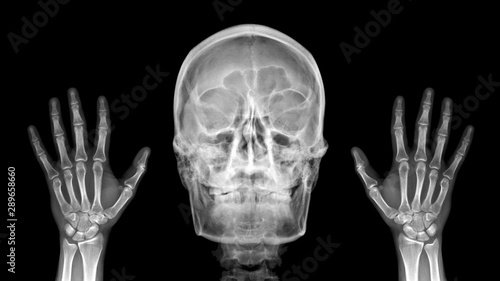

Film X Ray Radiograph Show Human Anatomy Of Skull Bone And